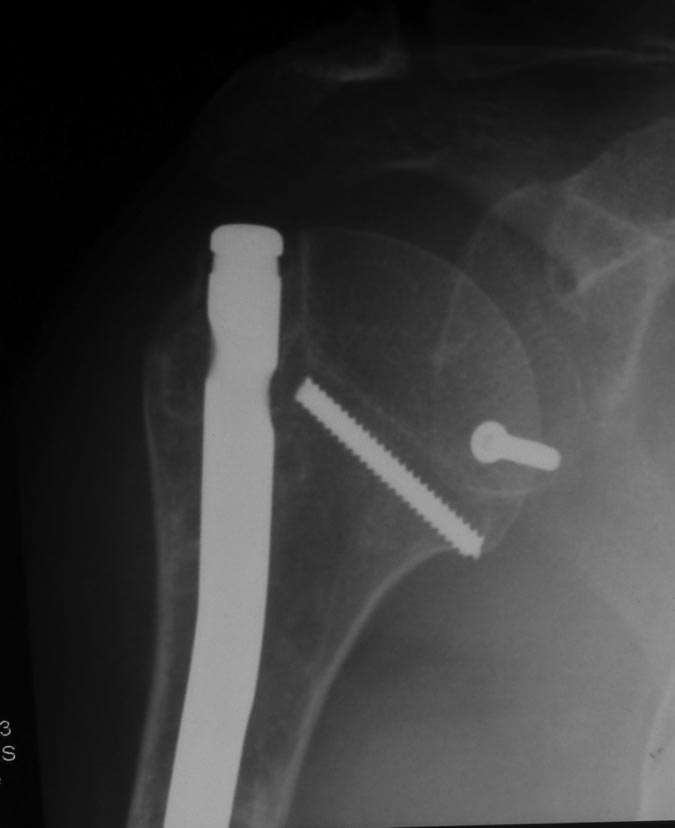

Уважаемые коллеги! Пациент получил травму около 1 года назад, выполнялся остеосинтез по поводу переломов лучевой, бедренной, плечевой костей. Обратился в связи с выраженной контрактурой в коленном суставе (сгибание 10-15 град)и практически отсуствием самостоятельного отведения плеча. Снимки представлены. Планируем выполнить реостеосинтез плеча (скорее всего этим же стержнем, так как другого нет) с коррекцией положения отломков в проксимальном отделе и сближением отломков в области диафиза. По надколеннику пока одна идея - его удаление. Хотелось бы услышать мнение и советы участников форума. - необходима ли будет костная пластика в области диафиза плеча? - адекватен ли по Вашему мнению реостеосинтез стержнем? - какая тактика в отношении ротационной манжеты? - приведет ли удаление надколенника и релиз сустава к существенному улучшению функции? Спасибо.

Надколенник-то, когда сломался? Не при редрессации-ли? Синтез плеча изначально сделан сикось-накось, надо переделывать, стержень - слишком длинный (видно вбили что есть), его использовать не удастся. То место, откуда торчит проксимальный конец стержня с винтами к вращательной манжете отношения не имеет - это немного выше, у бугорков. А что за радикализм в отношении надколенника? Удивляет то, что это пока единственная идея, пришедшая в голову автора;). Надо делать синтез, при этом и осуществить артролиз, а дальше видно будет.

Снимки бы почетче в обеих проекциях увидеть, и на всем протяжении - пока одна мутная проекция, дистального конца ни стержня, ни плечевой кости нет. Функциональные снимки делали, в максимальном отведении? Дефицит отведения только за счет варусной деформации, то есть проксимальный отдел плеча отводится нормально?

Как бы автор вопроса не убеждал себя, что в ситуации с гвоздем (его длиной, расположением относительно манжеты и бугорков и т.д.) все ясно, при таком качестве представленных рентгенограмм в единственной проекции никакой ясности быть не может.

В качестве примера - случай, который оперировал всего 2 недели назад, после похожего остеосинтеза, выполненного год назад. Пациентке 75 лет, тяжелый РА, легла для решения вопроса о ревизии тазобедренного сустава и заодно пожаловалась на то, что рука "крутиться" сама по себе, не поднимается. И болит, конечно. И посмотрите на разницу в информации на снимках головки плеча в двух противоположных проекциях. Даже комментировать ничего не нужно.